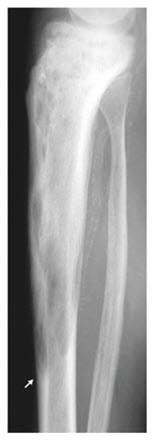

Sykdomsforandringer, lesjoner, kan finnes på ett sted eller flere steder i skjelettet. Tilstandén utvikler seg over tre faser. Første fase er økt nebryting av beinvev (økt osteoklastaktivitet), på røntgen ses det som mørkere flekker, lytiske lesjoner. I neste fase repareres dette med økt oppbygging av nytt beinvev, men dette beinvevet er mer uordnet enn normalt beinvev og det er mekanisk svakere. I siste fase forkalkes lesjonene, de beskrives som sklerotiske og fremstår som lysere på røntgen.

Tilstanden kan ramme flere ben hos samme pasient. På grunn av økt blodforsyning vil benet være varmt å ta på i de tilfeller der benet ligger tett opp til huden (for eksempel leggbeinet). Beinvevet kan være svært mykt eller svært hardt, og det kan være deformert på grunn av fortykkelse i beinet.

De knoklene hvor man hyppigst finner disse forandringene er leggbeinet (tibia), lårbeinet (femur), bekkenet (pelvis), ryggsøylen eller kraniet.